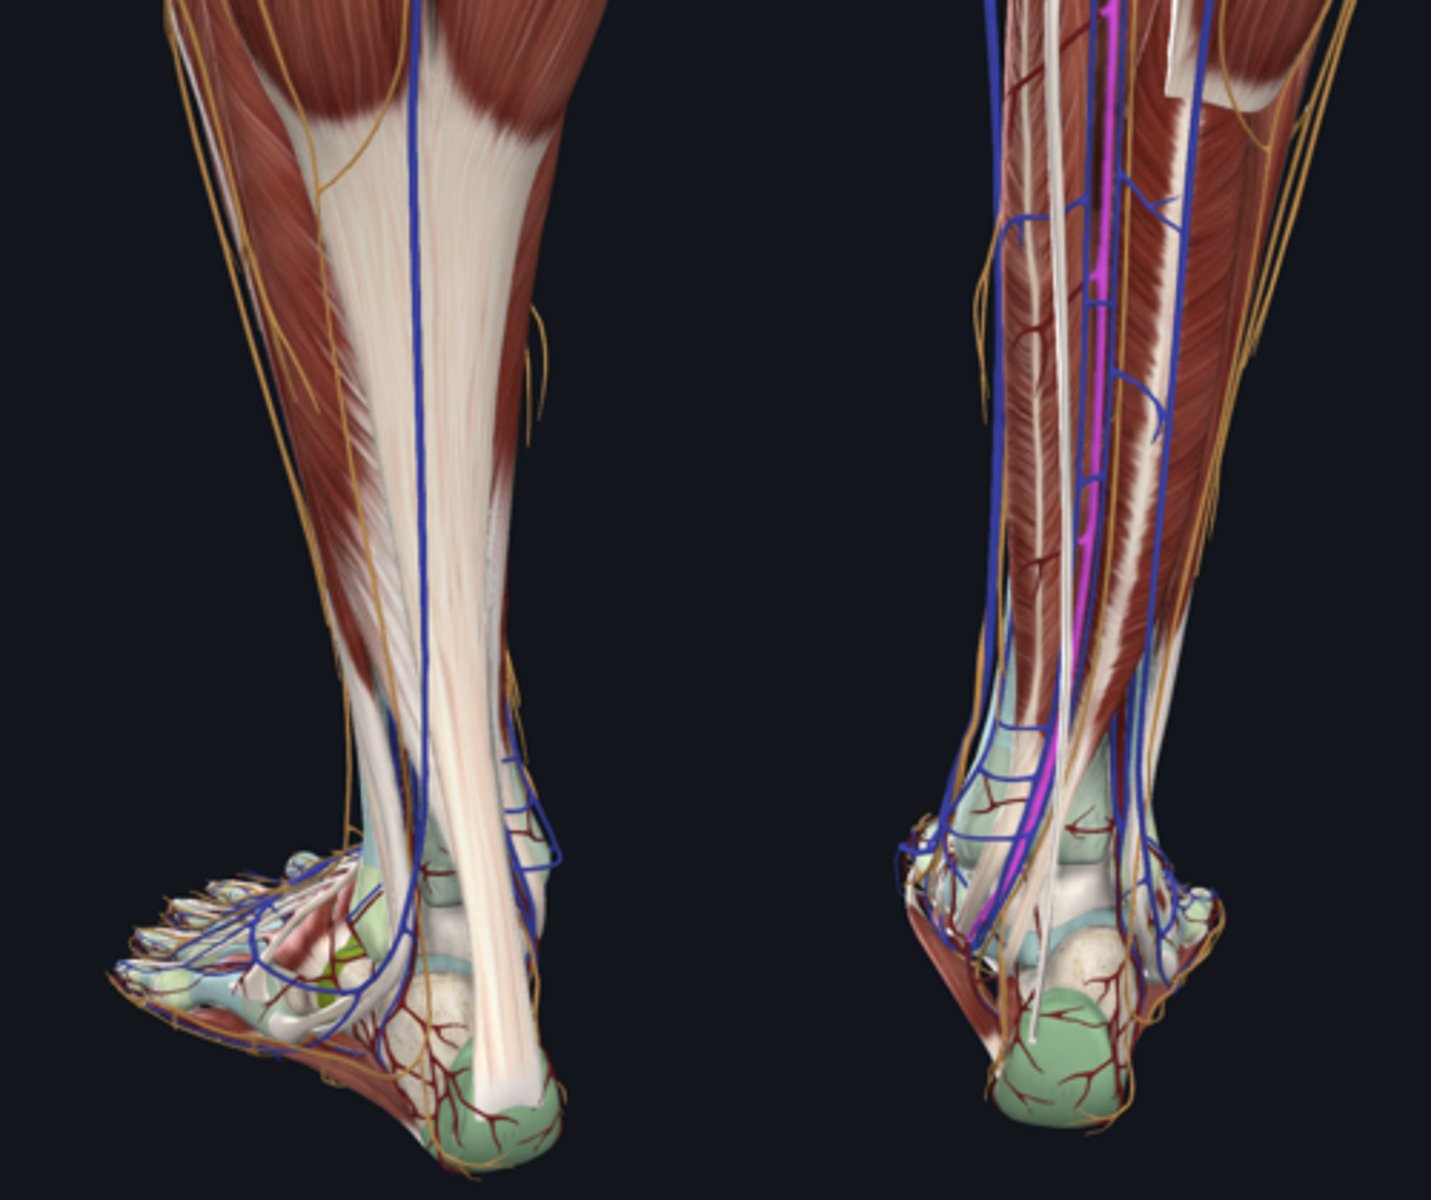

Tibial nerve (in tarsal tunnel)

nerve

Posterior tibial artery (in tarsal tunnel)

artery

Posterior tibial vein (in tarsal tunnel)

vein

Great saphenous vein

vein

Medial plantar nerve

nerve in pink

Lateral plantar nerve

nerve in pink